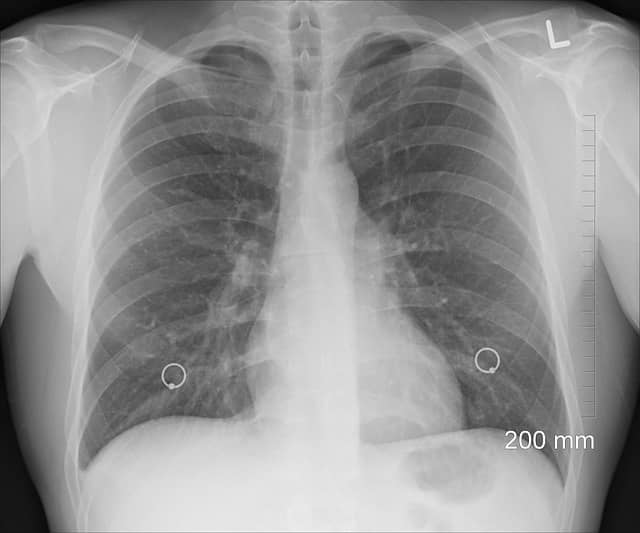

✅ 즉시 병원 이송 후 영상 검사(CT, X-ray)로 진단 & 흉관 삽입 필요!